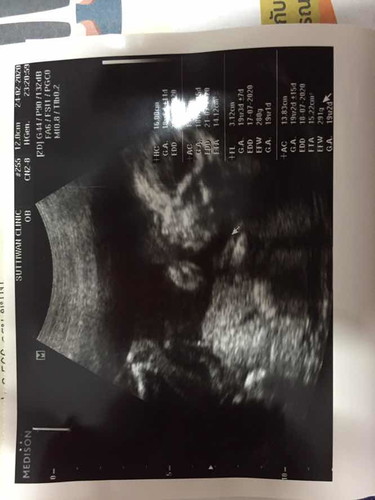

ลูกดิ้นเก่งมากค่ะ

ตอนนี้ได้5เดือนเต็มแล้วค่ะลูกดิ้งเก่งมากเลยค่ะ